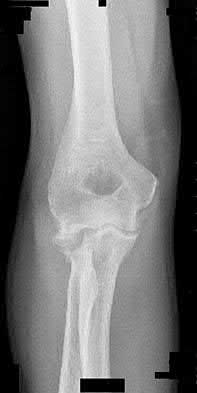

Excision is generally not indicated in this clinical scenario Corrent answer: 5

The injury likely represents a terrible triad injury. Restoration of the lateral column is required to restore valgus stability. A repaired or replaced radial head is also thought to be protective of the coronoid fracture repair. Therefore, excision is not indicated. Either radial head arthroplasty or open reduction and internal fixation would be indicated.